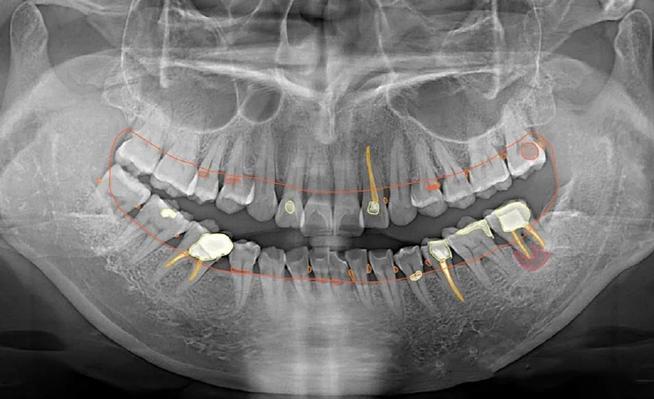

口腔正畸X光检查主要分为三类,各有其独特价值,曲面断层片(全景片)是最常用的基础检查,能一次性显示全口牙齿、牙槽骨、上下颌骨及部分颌面部结构,可观察是否有埋伏牙、多生牙、牙根吸收、牙槽骨骨密度异常等问题,辐射剂量低(约0.02mSv),相当于自然环境中2-3天的辐射量,适合常规筛查,头颅侧位片则是正畸诊断的“测量核心”,通过标记特定的解剖点(如蝶鞍、鼻根、上齿槽座点等),可定量分析上下颌骨的长度、宽度、高度比例,判断是否存在上颌前突、下颌后缩、面部不对称等问题,同时测量牙齿的倾斜角度、覆盖覆合程度,为矫治目标提供数据支持,CBCT(锥形束CT)则凭借三维成像优势,成为复杂病例的“精准导航”,能清晰显示牙根在颌骨内的位置、方向、形态,以及埋伏牙的萌出路径、骨量分布,适用于正颌手术前评估、种植体植入规划、疑难阻生牙拔除等场景,辐射剂量稍高(约0.1-0.3mSv),但单次检查仍在安全范围内,医生会严格掌握适应症。

| CBCT | 三维显示颌骨细微结构、牙根位置、骨量;复杂病例(正颌、种植)评估 | 三维高分辨率,精准定位 | 辐射较高,成本较高 |